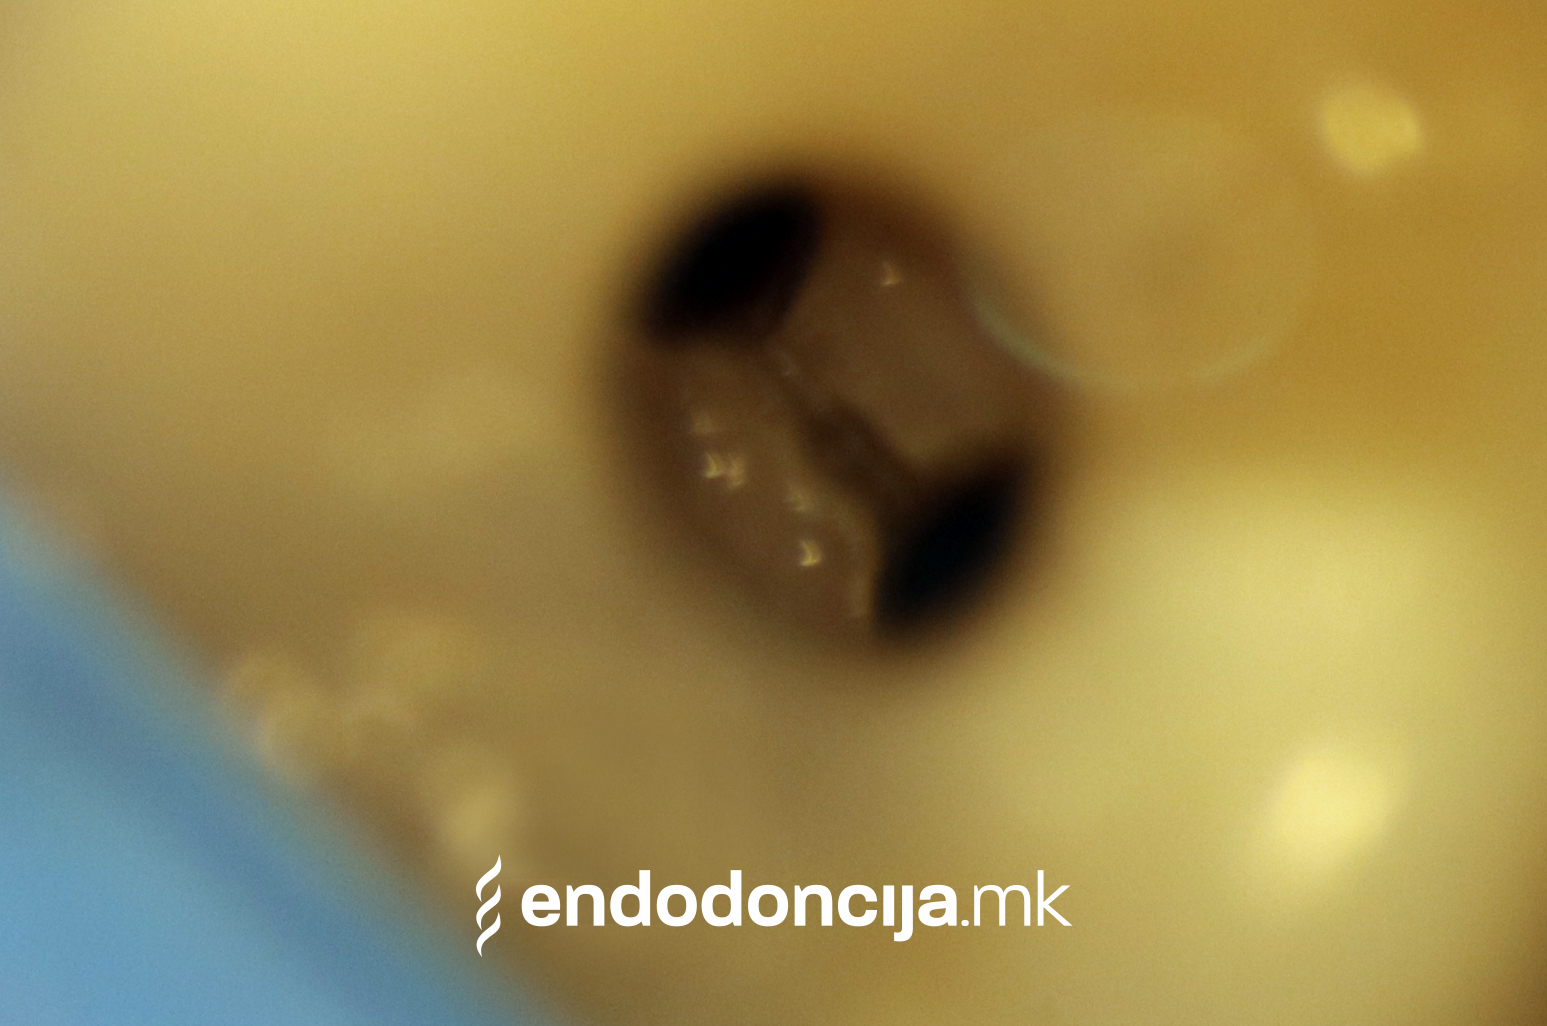

За време на претходните третмани, забот не само што бил ослабен со механички третман на коренскиот канал, туку и со поставување и закотвување на забното колче. Кога се ревидира третманот со коренскиот канал, овие колчиња треба да се отстранат колку што е можно повнимателно за да се задржи важната забна супстанција.

Она што е импресивно е прецизноста на микроскопските третмани. Дури и кога каналите се потешко достапни, може да се лоцираат и исчистат така што релапсите се со помала веројатност. Спротивно на тоа, скриените канали често остануваат неоткриени во конвенционалниот третман на коренскиот канал и затоа не можат да се чистат. Бактериите можат да се размножуваат таму без пречки и да предизвикаат воспаленија. Ова често останува незабележано со години додека не се појави забоболка, а со тоа и компликации.

Употребата на микроскоп исто така овозможува детектирање пукнатини или фрактури што може да предизвикаат болка или воспаление.